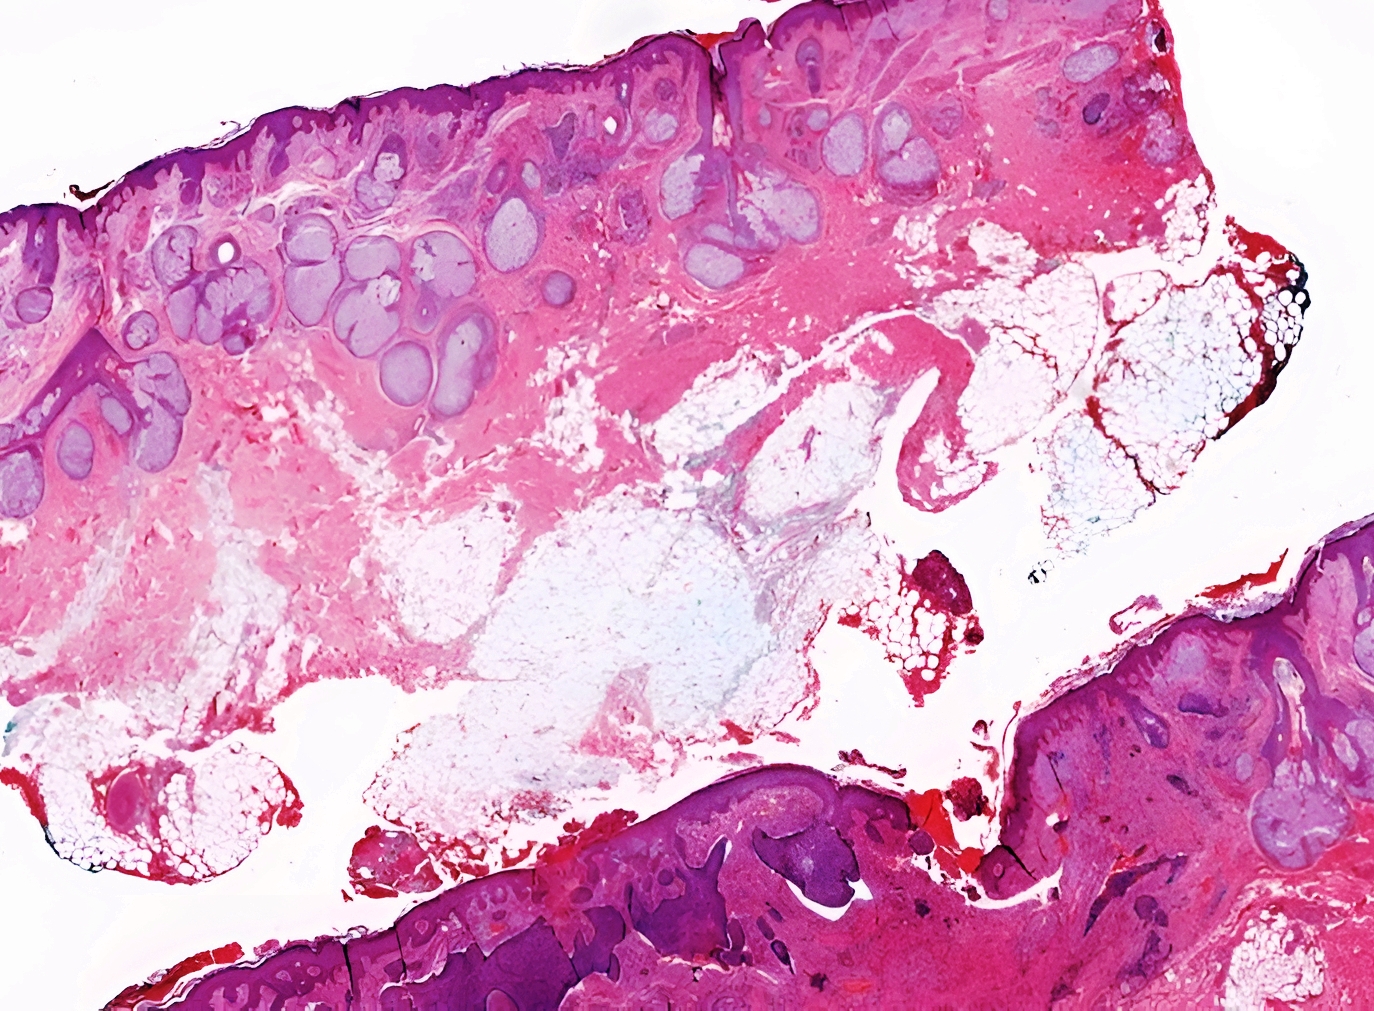

Freedom Nano Pathology is Innowave Healthcare’s advanced module for digital pathology management, built on the robust Freedom Nano PACS platform. Designed for the future of diagnostic medicine, it transforms conventional pathology labs into streamlined, image-driven diagnostic hubs. With the growing adoption of Whole Slide Imaging (WSI), telepathology, and AI-based diagnostics, Freedom Nano Pathology offers a centralized, scalable, and cost-effective solution to manage digital slides, reports, and workflows across pathology departments.

- AI Integration: Analyze histopathology images with AI tools for rapid detection of abnormalities such as cancer markers.

- AI Compatibility: Supports integration with external AI engines for inference on histopathological images.